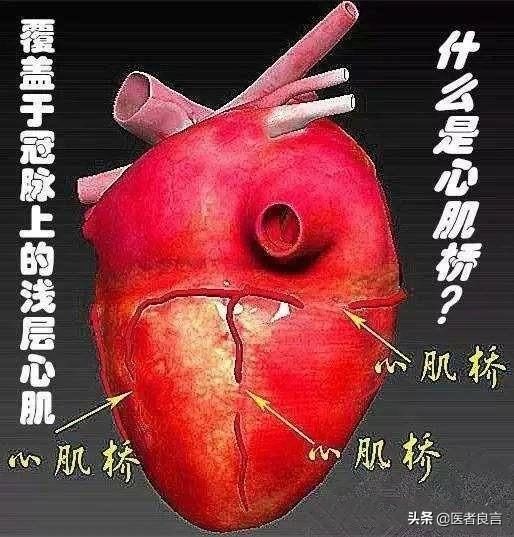

1.心筋ブリッジ:

私は以前、循環器内科のインターンシップでこのような患者に遭遇し、彼は心筋ブリッジと胸の締め付けが原因です。心筋ブリッジは多くの人が理解していないと推定され、ここでこの血管が心臓の内側にある通常の時間を参照するために心臓の表面に長い血管の心臓への血液供給を指し、血管の心臓の表面に長いアーチ型の橋に似ているので、医療専門家はそれを心筋ブリッジの名前を与えるために;心臓の心臓が鼓動するとき心臓が拍動しているとき、この血管が圧迫され、心臓への血液供給が減少するため、胸が締め付けられるような痛みが生じます;

最終まとめ:冠動脈造影検査で冠動脈狭窄が発見されず、なおかつ胸が締め付けられるような症状を示す場合は、心筋ブリッジ、心不全や不安定狭心症、肺疾患が原因である可能性がある。